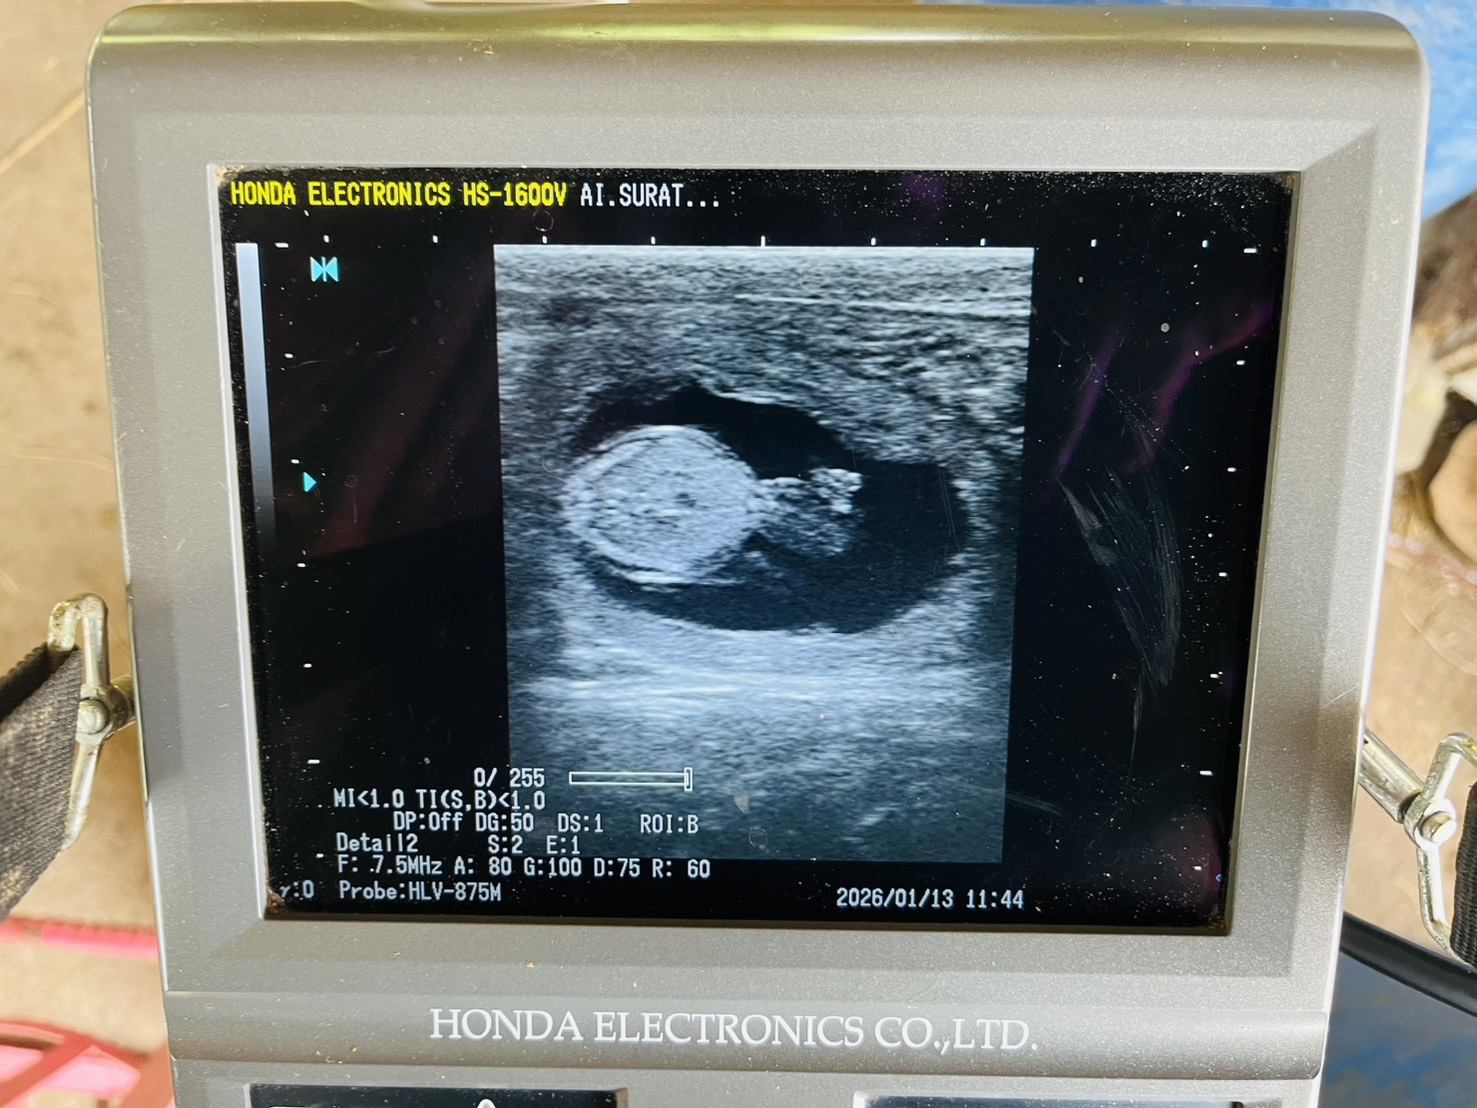

-ตรวจท้องโคนม

-ล้วงตรวจ/แก้ไขปัญหาระบบ สืบพันธุ์และฉีดวิตามินบำรุง